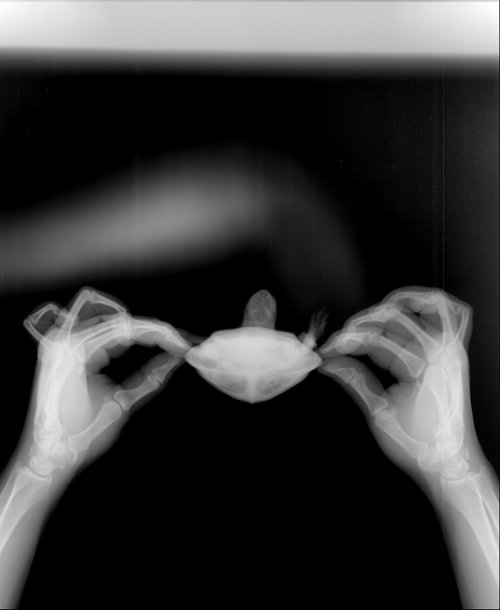

Юля48 Ваше имя: Юля Локация: Липецк Опубликовано: 25 июля 2019 Автор Опубликовано: 25 июля 2019 @moth добрый день! сделали рентген. Не знаю , так или нет. У нас только в одном месте его делают. Врач на нас как на инопланетян смотрел с черепахой . первый снимок вобще ничего не понятно(((

Консультанты moth Ваше имя: Мария Локация: Москва Опубликовано: 25 июля 2019 Консультанты Опубликовано: 25 июля 2019 @Юля48 я обработала немного снимки для четкости, выложите их в группу. Там точно по-моему газы есть и ещё что-то непонятное, нужно чтобы Артём посмотрел.

Юля48 Ваше имя: Юля Локация: Липецк Опубликовано: 26 июля 2019 Автор Опубликовано: 26 июля 2019 (изменено) @moth Добрый день! ответил врач по снимкам. "есть признаки, как вздутие жкт, так и пневмонии. Я бы начал курс инъекций антибиотика (байтрил, марфлоксин). Так же внутрь задать несколько раз эспумизан суспензию. Но это сложная процедура. Елец, это липецкая область. При возможности, стоит добраться до врачей в Липецке или Тамбове, занимающихся лечением рептилий, для оценки состояния черепахи" Не подскажете в какое место точно колоть антибиотик? шприц самый маленький нужен ? И если эспумизан давать , то как? Изменено 26 июля 2019 пользователем Юля48

Юля48 Ваше имя: Юля Локация: Липецк Опубликовано: 22 августа 2019 Автор Опубликовано: 22 августа 2019 (изменено) @moth Добрый день! Мария,Мы повторили рентген . Отправила в группу , но пока ждем ответа , может вы что-то подскажете. Врач на рентгене сказал что легкие хорошие, антибиотик помог (Кололи Байтрил почти месяц как сказал Артем) .Но у нас еще другая проблема . Пневматоз кишечника. На снимке явно видно большие каловые массы и вздутие. Как можно помочь с туалетом ему? общее состояние без изменений. Не ест, не какает, лапы задние для передвижения не использует, плавает по дну. Разве что , немного меньше стал раздувать шею. Изменено 22 августа 2019 пользователем Юля48